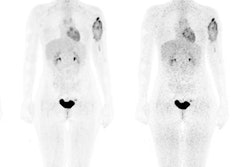

Whole-body therapeutic (Re-186 HEDP) and diagnostic (Tc-99m) bone scans of a patient with bone metastases. All images courtesy of Ana Denis-Bacelar.But physiology differs from patient to patient, and as a result, the absorbed dose can vary by up to two orders of magnitude. "Dosimetry is not mandatory and is not usually performed, because it hasn't been proved to be useful in large randomized clinical trials. But we can't prove that it is useful if we don't do it," she pointed out.